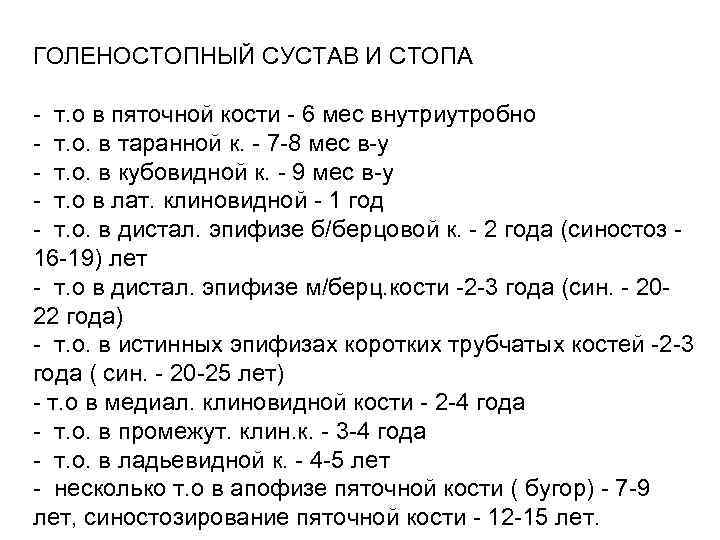

ГОЛЕНОСТОПНЫЙ СУСТАВ И СТОПА - т. о в пяточной кости - 6 мес внутриутробно - т. о. в таранной к. - 7 -8 мес в-у - т. о. в кубовидной к. - 9 мес в-у - т. о в лат. клиновидной - 1 год - т. о. в дистал. эпифизе б/берцовой к. - 2 года (синостоз 16 -19) лет - т. о в дистал. эпифизе м/берц. кости -2 -3 года (син. - 2022 года) - т. о. в истинных эпифизах коротких трубчатых костей -2 -3 года ( син. - 20 -25 лет) - т. о в медиал. клиновидной кости - 2 -4 года - т. о. в промежут. клин. к. - 3 -4 года - т. о. в ладьевидной к. - 4 -5 лет - несколько т. о в апофизе пяточной кости ( бугор) - 7 -9 лет, синостозирование пяточной кости - 12 -15 лет.

ГОЛЕНОСТОПНЫЙ СУСТАВ И СТОПА - т. о в пяточной кости - 6 мес внутриутробно - т. о. в таранной к. - 7 -8 мес в-у - т. о. в кубовидной к. - 9 мес в-у - т. о в лат. клиновидной - 1 год - т. о. в дистал. эпифизе б/берцовой к. - 2 года (синостоз 16 -19) лет - т. о в дистал. эпифизе м/берц. кости -2 -3 года (син. - 2022 года) - т. о. в истинных эпифизах коротких трубчатых костей -2 -3 года ( син. - 20 -25 лет) - т. о в медиал. клиновидной кости - 2 -4 года - т. о. в промежут. клин. к. - 3 -4 года - т. о. в ладьевидной к. - 4 -5 лет - несколько т. о в апофизе пяточной кости ( бугор) - 7 -9 лет, синостозирование пяточной кости - 12 -15 лет.